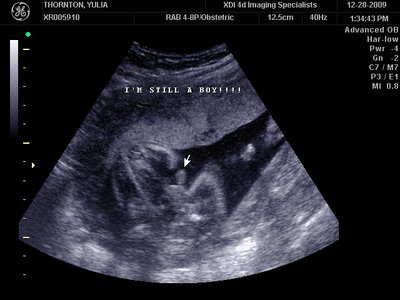

Ну ладно, тогда и я нашего писюна покажу  Надеюсь, Джеффри на меня не обидится Вот это в 23 недели: (там оборудование переключалось из режима 3Д в обычный 2Д)

| Вложения: |

MY BABY SONO!_2_15.JPG [ 112.35 КБ | Просмотров: 1036 ]

Sweetheart75 писал(а): Ну ладно, тогда и я нашего писюна покажу  Надеюсь, Джеффри на меня не обидится Вот это в 23 недели: (там оборудование переключалось из режима 3Д в обычный 2Д) Oоо, такое достоинство невозможно не заметить  А в 30 недель так вообще!